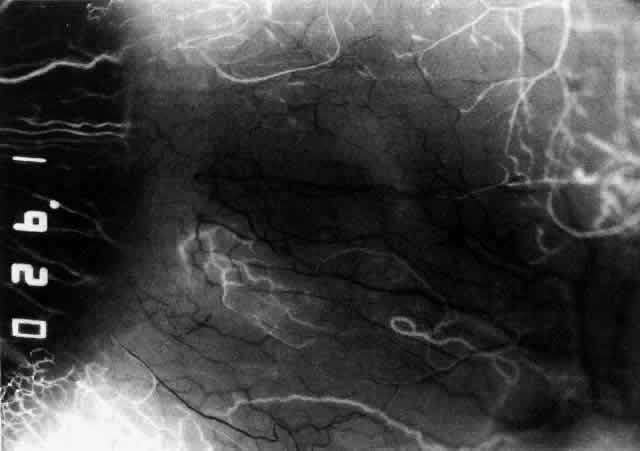

Fig. 33. Fluorescein angiogram of patient in Figure 32 four seconds after the appearance of the dye. This is a very rapid transit

time. All the limbal capillaries are completely full, and all the

major episcleral vessels contain fluorescein. Note that the very large

vessel is a vein, and the narrow vessel below it is an artery. The deep

vessels are distorted, and some are abnormal in configuration. Fig. 33. Fluorescein angiogram of patient in Figure 32 four seconds after the appearance of the dye. This is a very rapid transit

time. All the limbal capillaries are completely full, and all the

major episcleral vessels contain fluorescein. Note that the very large

vessel is a vein, and the narrow vessel below it is an artery. The deep

vessels are distorted, and some are abnormal in configuration.

|